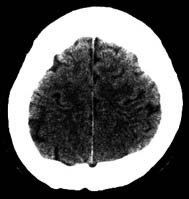

頭部CT

X線を使用する撮影ですが、細いX線ビームを回転しながら出してそれをコンピュータ画像処理したものです。

スライス番号は、すぐ下のCT画像に対応しています。上段の図をクリックすると下段のCT画像が拡大して見られます。